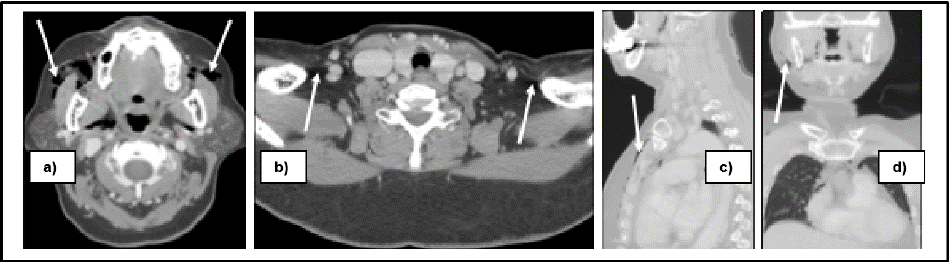

The clinical impression was consistent with extensive surgical emphysema secondary to the surgical removal of dental implants. The patient was admitted for close airway monitoring. Management included the administration of supplemental oxygen and the initiation of intravenous analgesic and prophylactic antibiotics – specifically ceftriaxone and metronidazole. There was no progression of the emphysema, allowing for the continuation of conservative management (Figure 3).

Figure 3: A follow up CT scan on postoperative day seven was demonstrated significant improvement on subcutaneous emphysema, with minimal air was

remained.

On day seven, a follow-up CT scan was done. The subcutaneous emphysema was almost resolved dramatically, with only minimal residual air was remained. The retained implant fragment was performed under local anesthesia without complication. The patient continued to recover and was discharged on day nine with instructions for outpatient follow-up until complete clinical and radiographic resolution of the subcutaneous emphysema (Figure 4).